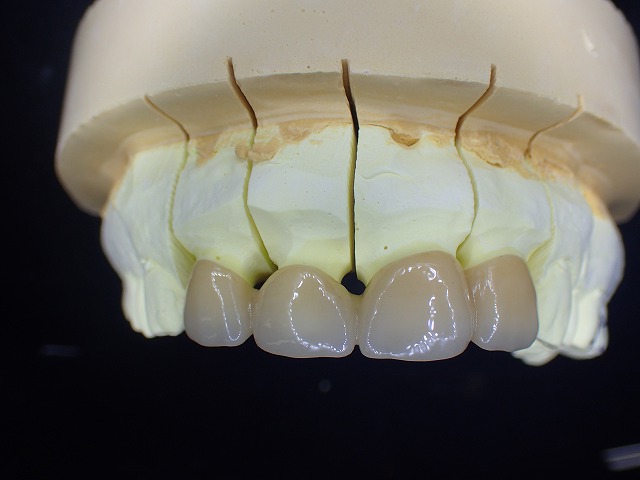

脱離を繰り返している歯なので

今回はジルコニアクラウンを脱脱防止のために

連結して制作します。

通常の状況では連結冠は制作しませんが

海外で脱離するリスクを考慮して連結冠としました。

技工物完成

今回も最低限の厚みで制作してあります。